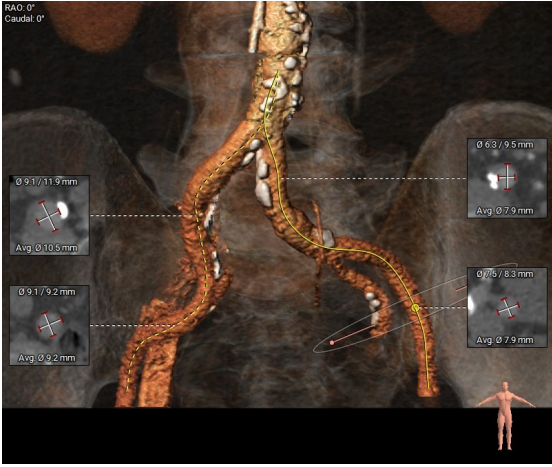

入路情况

● 入路情况:主动脉弓部较平缓,主动脉弓部可见少许钙化斑块,过弓需谨慎,主动脉弓部三根分支动脉开口未见明显狭窄征象、未见发育变异,胸主动脉、腹主动脉较平直,胸主动脉、腹主动脉可见少许钙化及非钙化斑块,管腔未见明显狭窄,双侧髂动脉稍迂曲,可见少许钙化及非钙化斑块,管腔未见明显狭窄,股动脉入路两侧血管无迂曲,右侧入路血管分叉高。左侧血管平均最小内径7.3mm,右侧血管平均最小内径7.5mm。建议以右侧股动脉为主入路。右侧分叉高建议外科切开;如选择穿刺入路,建议左侧股动脉。